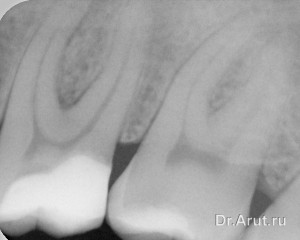

Лечение: трепанация зуба через пломбу, вскрытие полости зуба, ампутация и экстирпация пульпы, инструментальная и медикаментозная обработка корневых каналов. Каналы запломбированы гуттаперчевыми штифтами с AH plus методом вертикальной конденсации. Коронковая часть зуба восстановлена композиционным пломбировочным материалом.

- Пломбирование каналов зуба